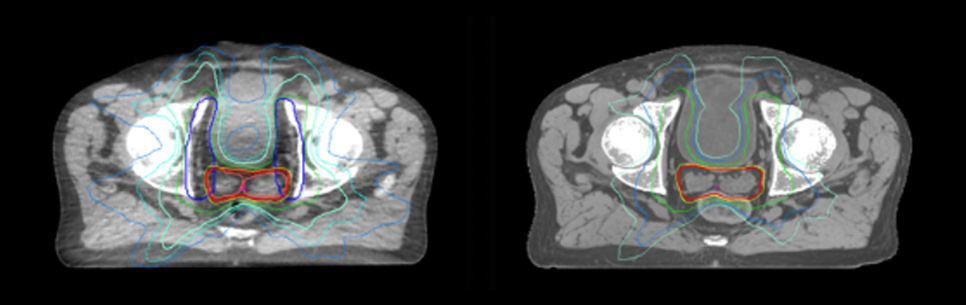

Dose plans overlaid on CBCT image dataset (left) and on MRCAT image dataset (right).

Dosimetric equivalence validation was performed on 43 patient cases by comparing MRCAT-based dose plans overlaid on CBCT image dataset and on the corresponding MRCAT image dataset. Mr. Bolard and Dr. Champion found good agreement between MRCAT-based and CT-based dose calculations, with a mean dose ratio of 1.007 (0.991-1.014). The 3D gamma score was greater than 95% (95.2-99.0%) for all plans checked. A poster on this work was accepted for presentation at ESTRO 2020.

Evaluation of MRCAT dosimetric accuracy

Mr. Bolard and Dr. Champion found good agreement between MRCAT-based and CT-based dose calculations, with a mean dose ratio of 1.007 (0.991-1.014).